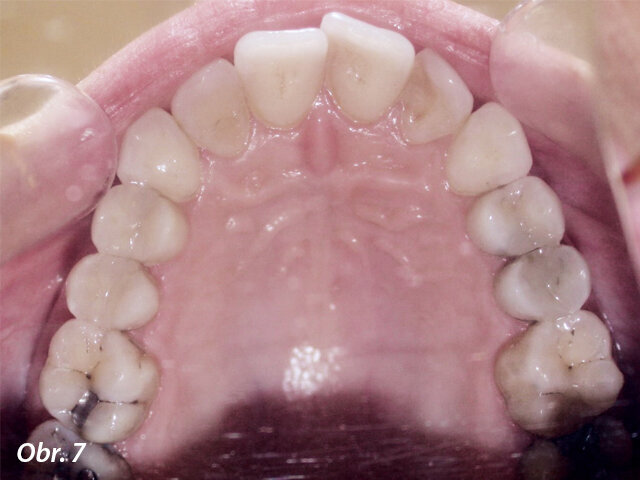

Dále byl vyhodnocen kefalometrický snímek (obr. 9), ortopantomogram (obr. 10) a provedena analýza modelů (obr. 11–15).

Po naskenování modelů byl návrh léčebného plánu odeslán ke zhotovení zámků a drátěných oblouků. Protože byla plánována extrakce zubů 14, 24, 34 a 44, byly na zámky 17, 27, 37 a 47 požadovány háčky k usnadnění zavádění el. řetízků používaných ve fázi uzavírání mezer.

Byly zvoleny tyto drátěné oblouky pro jednotlivé fáze léčby:

Nivelizace NiTi .014, NiTi .016 × .022

Pro zvýšení torze před fází uzávěru mezer byl použit NiTi .017 × .025.

Pro konsolidaci zbytkových mezer byl použit ocelový oblouk .017 × .022.

Závěrečná fáze léčby proběhla na oblouku TMA .175 × .175.